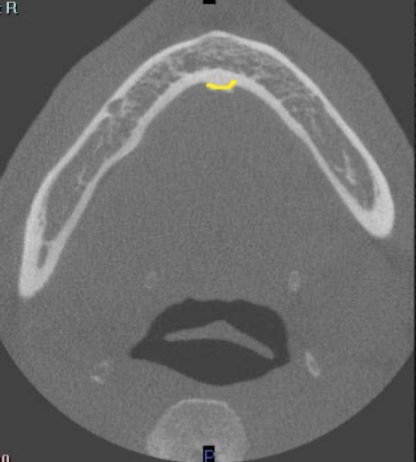

beeam hardening (braces)

what is the cause of this artifact

increase number of views and exposure (increase #xrays and dose)

what can you do to decrease artifact